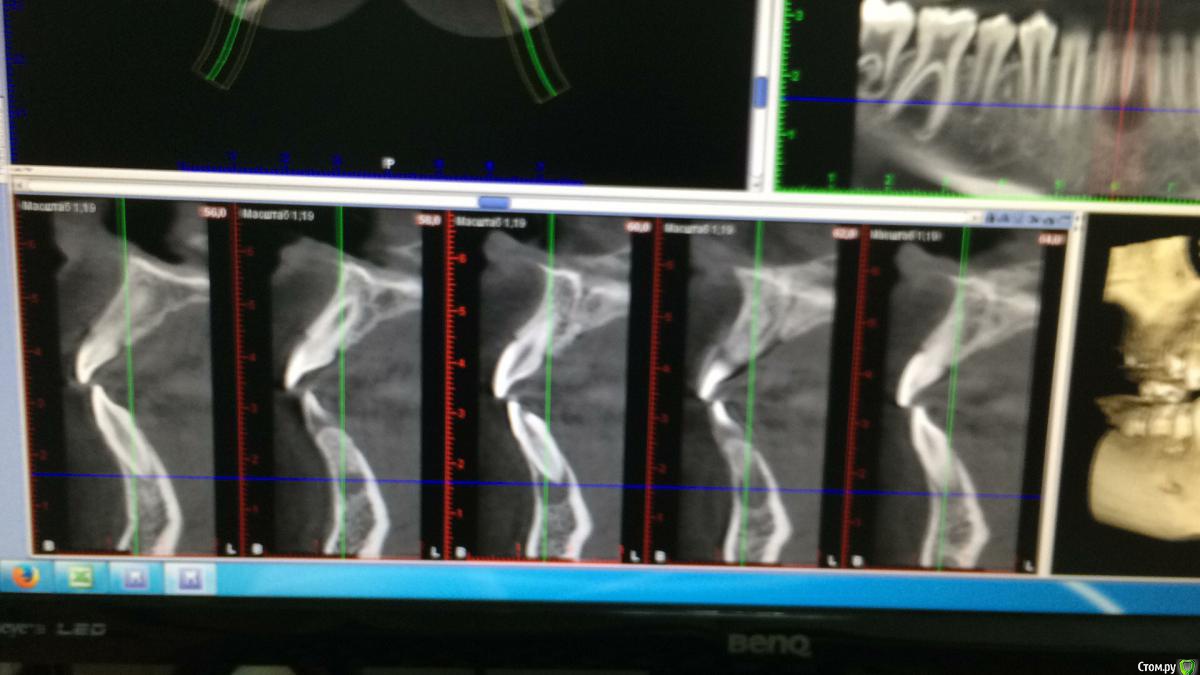

DenisV Опубликовано 16 февраля, 2017 Автор Поделиться Опубликовано 16 февраля, 2017 Коллеги кто что думает? Мальчик 12 лет обратился с жалобами на боль в зубе 4.1, зуб раскрыт, получен эксудат из канала.Зуб был ранее интактен в госке зуб открыли и назаначили полоскания, сейчас подвижность 2-3 степени. Мама отмечает ранее травму этого зуба. Ссылка на комментарий

Давлетшин Опубликовано 20 февраля, 2017 Поделиться Опубликовано 20 февраля, 2017 (изменено) Добавлю, что кажется, что канал раздваивается на середине корня, по фото плохо видно. Т.е. кальций в оба канала. и каналы очень хорошо мыть и УЗ. а по размеру разряжения не особо страшно.И что между 44 и 45? Изменено 20 февраля, 2017 пользователем Давлетшин Ссылка на комментарий